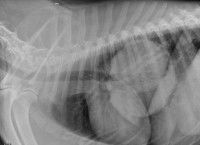

Pour détecter l'origine d'une maladie de l'appareil respiratoire du chien, le vétérinaire peut avoir recours à toute une batterie de tests :

Enfin, face à des symptômes liés au système respiratoire, une origine cardiaque est toujours envisagée, et des signes d'atteinte cardiaque sont recherchés. En effet, lorsque le coeur fonctionne mal, des modifications de la pression dans les vaisseaux sanguins ou encore du sang qui s'accumule dans les poumons peuvent gêner le bon fonctionnement de l'appareil respiraotire, et faire naître une difficulté respiratoire.